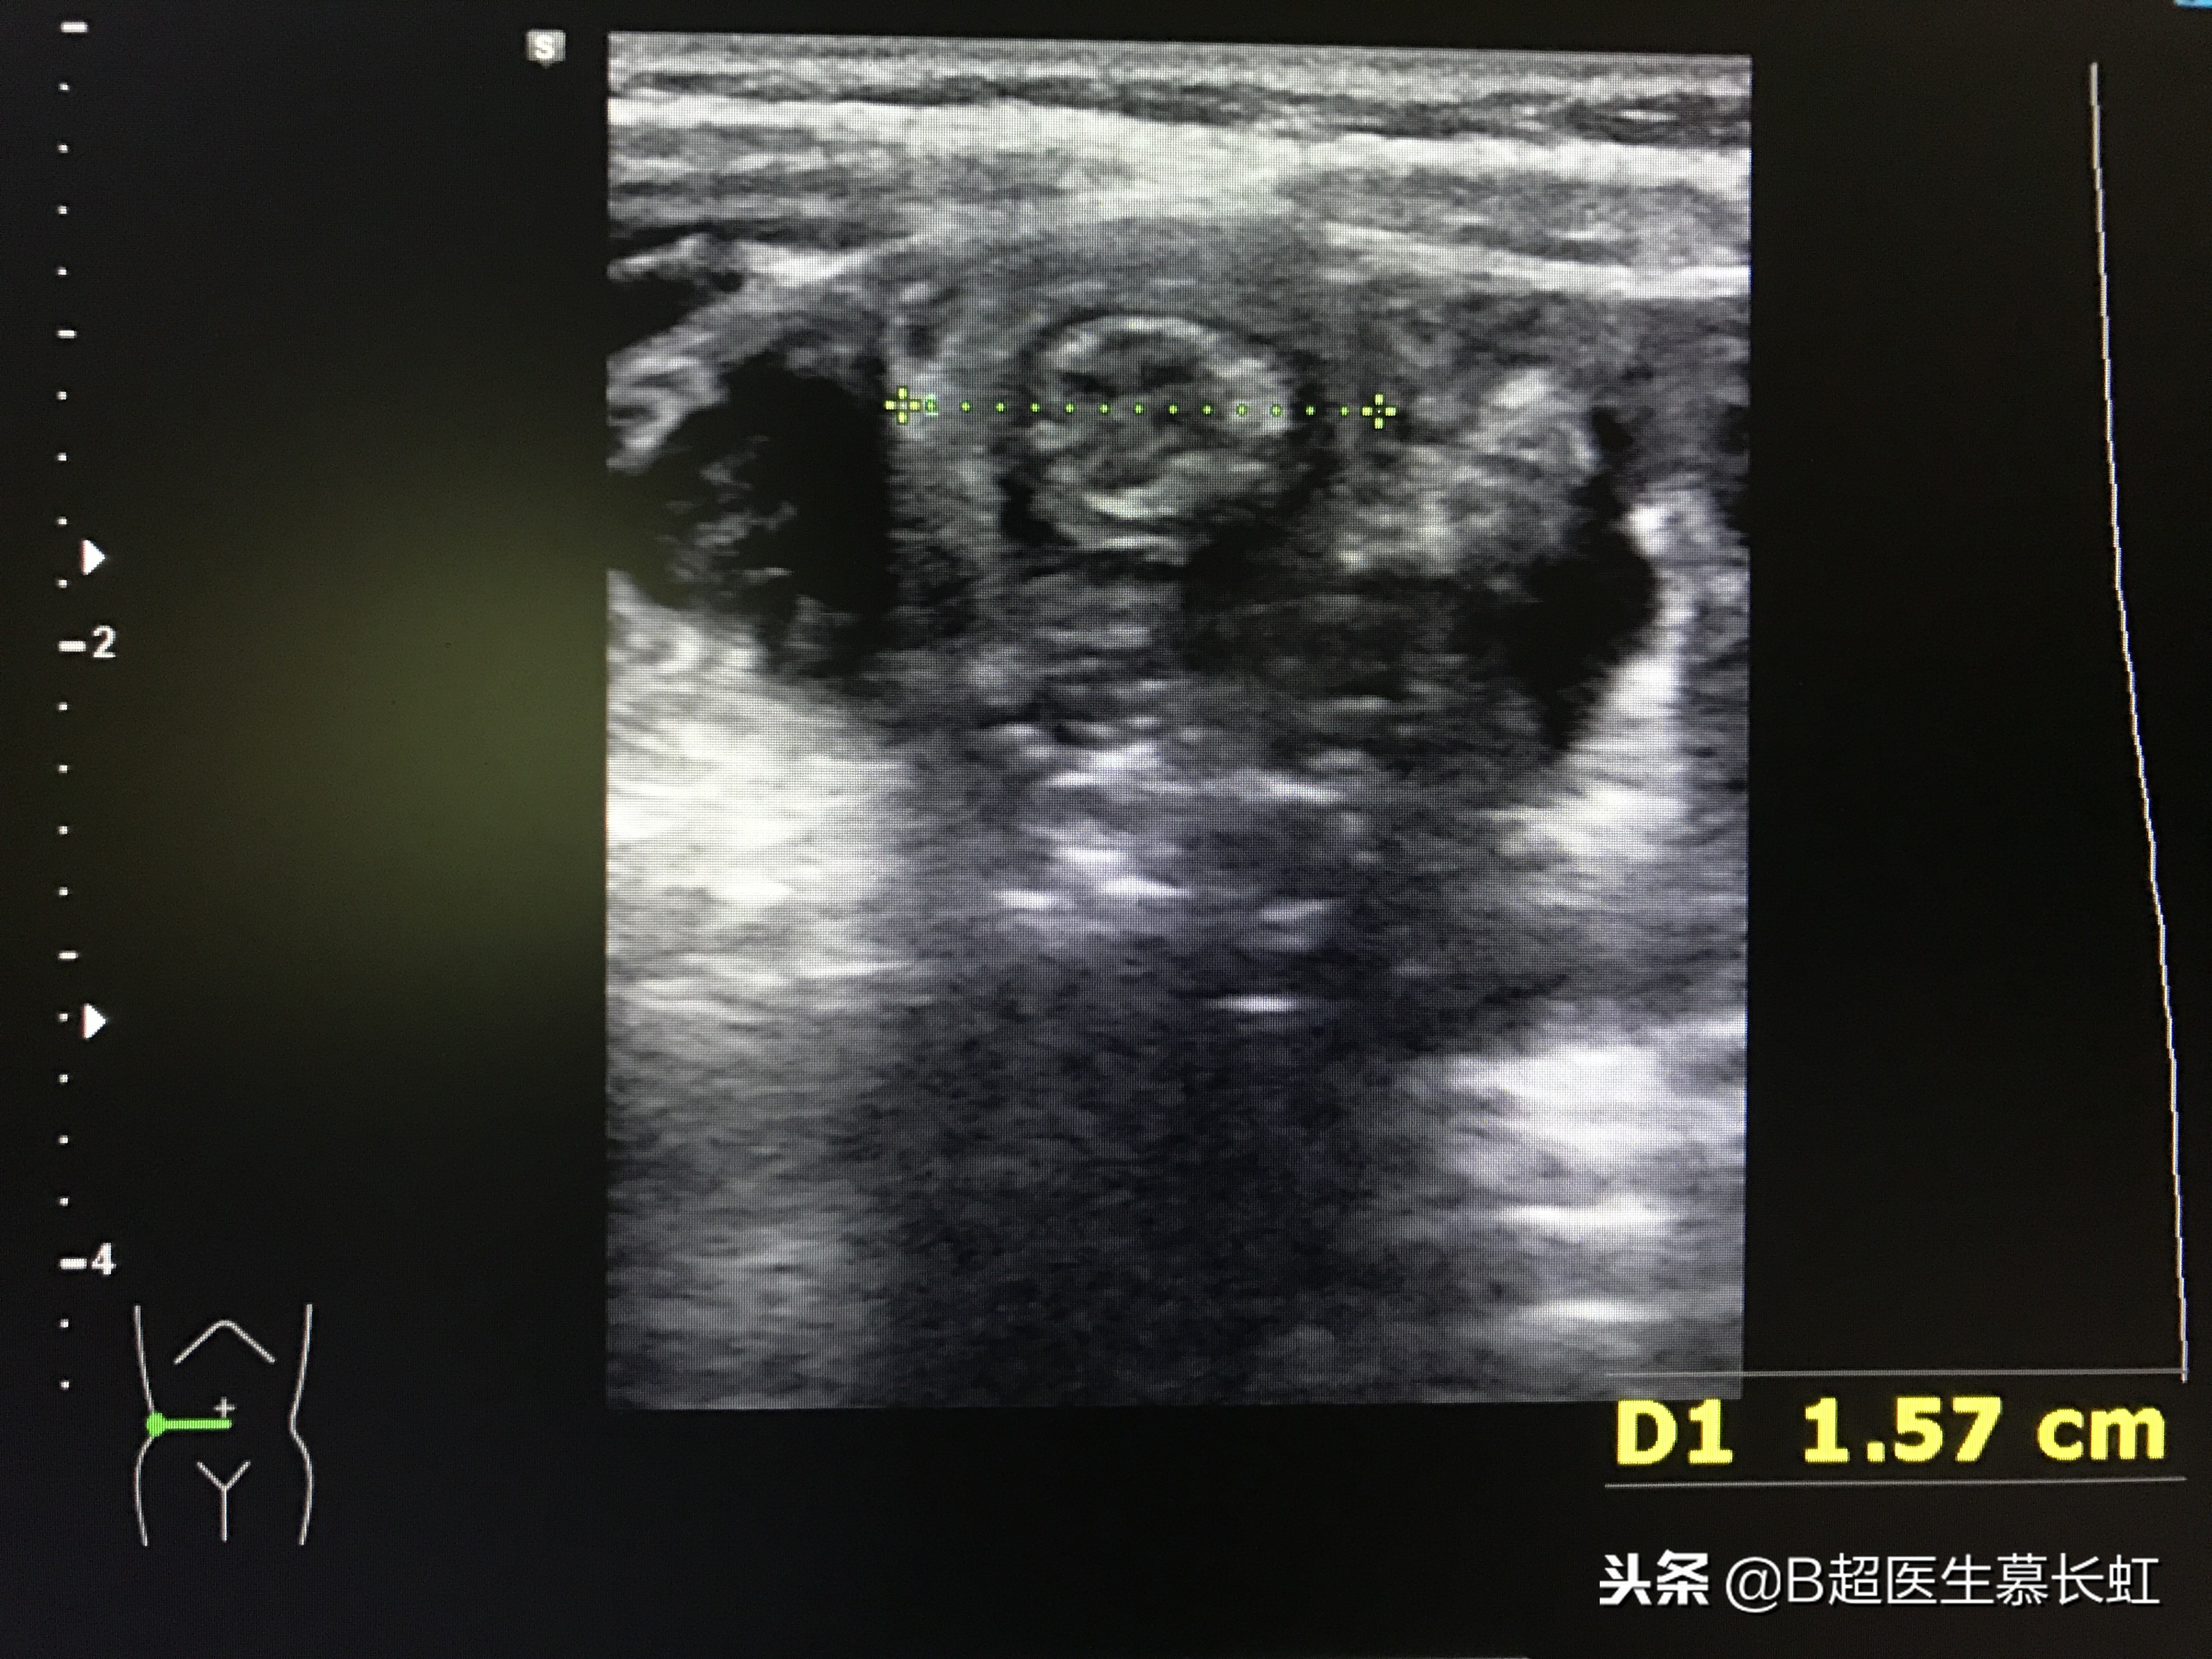

同心圆征

超声表现:1、同心圆征:肠壁水肿不严重。

同心圆征,两处肠套叠